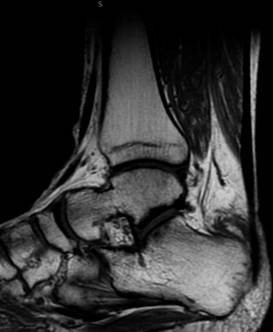

En nuestra primera consulta se envió a terapia física y rehabilitación realizando un total de ocho sesiones dentro de nuestra institución, no mostrando mejoría ni disminución del dolor, por lo que se solicitaron estudios de imagen, los cuales consistieron en radiografía anteroposterior y lateral de tobillo en la cual se evidenció adecuada congruencia de la articulación tibioastragalina y tibioperonea, exostosis posterosuperior de calcáneo de 6 milímetros de altura con relación a la línea articular superior, y alteraciones en la grasa de Kager (Figuras 1 y 2). De igual manera, se realizó resonancia magnética de tobillo evidenciando tendinitis aquílea, bursitis retrocalcánea y líquido en la bursa retroaquílea de aproximadamente 3 cm3. Se observa tendón aquíleo engrosado en su inserción y tendinitis insercional con edema óseo en región posterior de calcáneo (Figura 3).

Figura 3: Resonancia magnética simple de tobillo de corte sagital, se observa bursitis retrocalcánea y líquido de aproximadamente 3 cm3 en bursa retroaquílea.